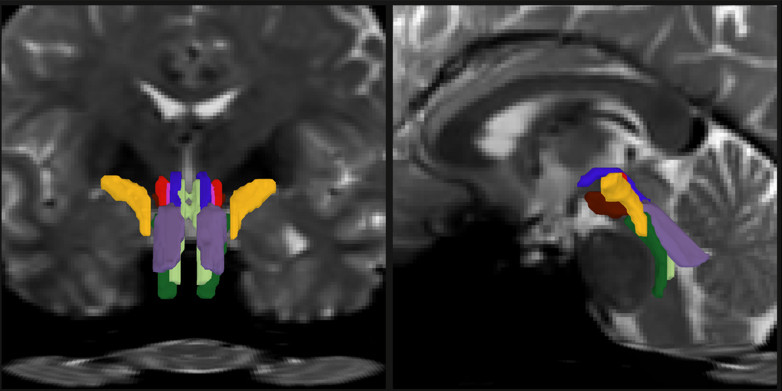

BSBT được thiết kế để vượt qua rào cản này. Thuật toán trước tiên dựng bản đồ xác suất các bó sợi đi từ những vùng não lân cận như đồi thị và tiểu não xuống thân não. Sau đó, một mạng nơ-ron tích chập (convolutional neural network) tích hợp bản đồ này với nhiều lớp dữ liệu hình ảnh khác để phân biệt tám bó sợi riêng biệt.

Sau giai đoạn huấn luyện, BSBT có thể tự động xác định tám bó sợi trong các bộ dữ liệu mới. Khi thử nghiệm trên 40 tình nguyện viên được chụp hai lần cách nhau hai tháng, công cụ này liên tục xác định chính xác cùng một hệ bó sợi ở mỗi cá nhân. Nhóm nghiên cứu cũng kiểm tra chéo trên nhiều bộ dữ liệu độc lập và đánh giá riêng từng thành phần của mạng nơ-ron để bảo đảm độ tin cậy.